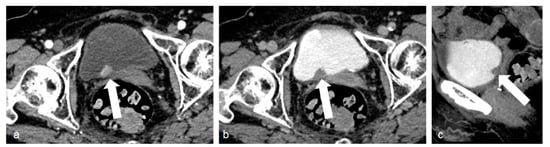

Figure 7.

Different 3D reconstructions of the excretory phase.

MIP reformations are constructed from the highest attenuation voxels in a dataset and projected into a 3D format. These reconstructions are particularly helpful in evaluating the collecting systems and ureters, allowing a complete and quick overview of the high-density contrast within the collecting systems, and highlighting subtle filling defects, focal thickening of the excretory system walls, luminal narrowing or strictures, calyceal abnormalities, hydronephrosis, and hydroureter.

Three-dimensional reconstructions provide specific colors to each voxel in a data set according to its attenuation and relationship to other adjacent voxels, allowing the visualization of the whole opacified excretory system. Some authors support their role in the identification of slight urothelial thickening, especially in cases of reduced excretion of the contrast into the collecting system, when MIP reformations are of limited usefulness [7,19,46].